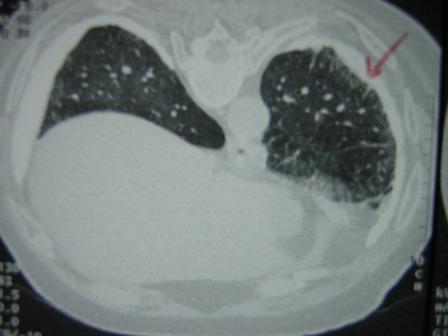

High Resolution CT scan of the lungs (Figure 2) showed bilateral pleural plaques, diffuse pleural thickening and increased interstitial markings. These changes were confirmed on prone films as well. (Figure 3) The calcified pleural plaques are particularly well seen on the mediastinal window of the CT scan (Figure 4).

Figure 4: CT scan of the thorax — mediastinal windows.